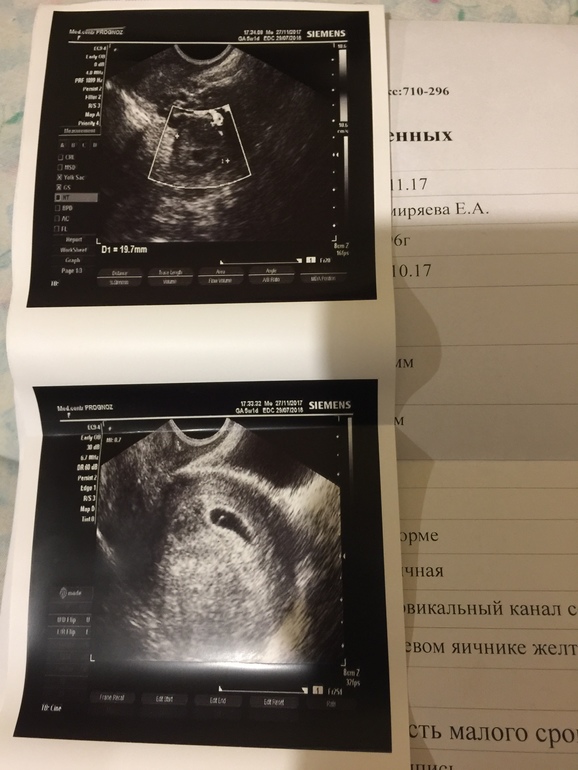

Всем привет, девочки, помогите или расскажите свои похожие истории, в общем дело в том что 4 дня назад делала УЗИ и там был пя 7 мм, без эмбриона и желточного мешочка, в итоге пошла сегодня жк и знакомая медсестра напугала что при таком размере пя эмбрион уже должен быть, в итоге поехала в другую клинику, сделала УЗИ, и пя 16 мм! За 4 каких то дня, но нашли желточный мешочек, и врач сказала что раз он появился значит беременность развивается, объяснила стадиями, сначала появляется пя, потом желточных мешок и только потом эмбрион, типа раз 2 стадия у тебя уже пошла то через недельку и эмбриона найдём. В общем 5 месяцев назад была зб и делали чистку, теперь всего боюсь как огня, уже час лежу плачу:(

это УЗИ 4 дня назад, а вот сегодняшнее

7 мм было 4 дня назад, сегодня делала пя 16 мм